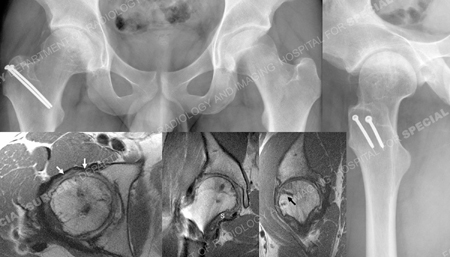

A Kocher-Langenbeck approach with a trochanteric flip and anterior dislocation of the hip was performed and the multiple fracture fragments were visualized. One was a free, thin osteochondral fragment found along the anterior surface of the femoral head. Considering the fact that the middle one-third of the femoral head was missing but involved the weight-bearing area, it was elected to obtain a frozen, femoral head osteochondral allograft. Once thawed, it was cut into place with an oscillating saw so as to fit into the defect. Autograft morselized bone was obtained from the greater trochanter and was placed underneath the allograft, the reconstructed medial femoral head fragment, and the osteochondral fragment. Two screws were placed into each loose fragment and aimed towards the intact femoral head. The screw heads were seated below the articular surface of the femoral head fragments. The femoral head was found to be congruous. The small, loose fragments from the periphery of the posterior wall were debrided as they were not felt to be requisite to the stability of the hip joint. The hip was located and congruity confirmed. He returned for regular follow-up visits and at 32 months and was working full time and returned to pre-injury activities. Radiographs of the hip showed a healed fracture of the femoral head and trochanteric osteotomy. There was a small amount of heterotopic ossification (Brooker stage I). There was no evidence of avascular necrosis (AVN). Crossing trabeculae were seen between the allograft and lateral femoral head with no evidence of collapse or ischemia in either.

Anteroposterior and lateral X-rays of hip 21 months after surgery and MRI images of hip 7 months after surgery; and MRI images (from left to right) axial MR image demonstrates restoration of femoral head contour after reduction and graft fixation and articular cartilage remains intact (white arrows), coronal MR image suggestive of graft having been incorporated, mild flattening of medial border with otherwise normal contour and synovitis evident; indicated with āsā, sagittal MR image; linear low signal (black arrow) is from Bionix screw.